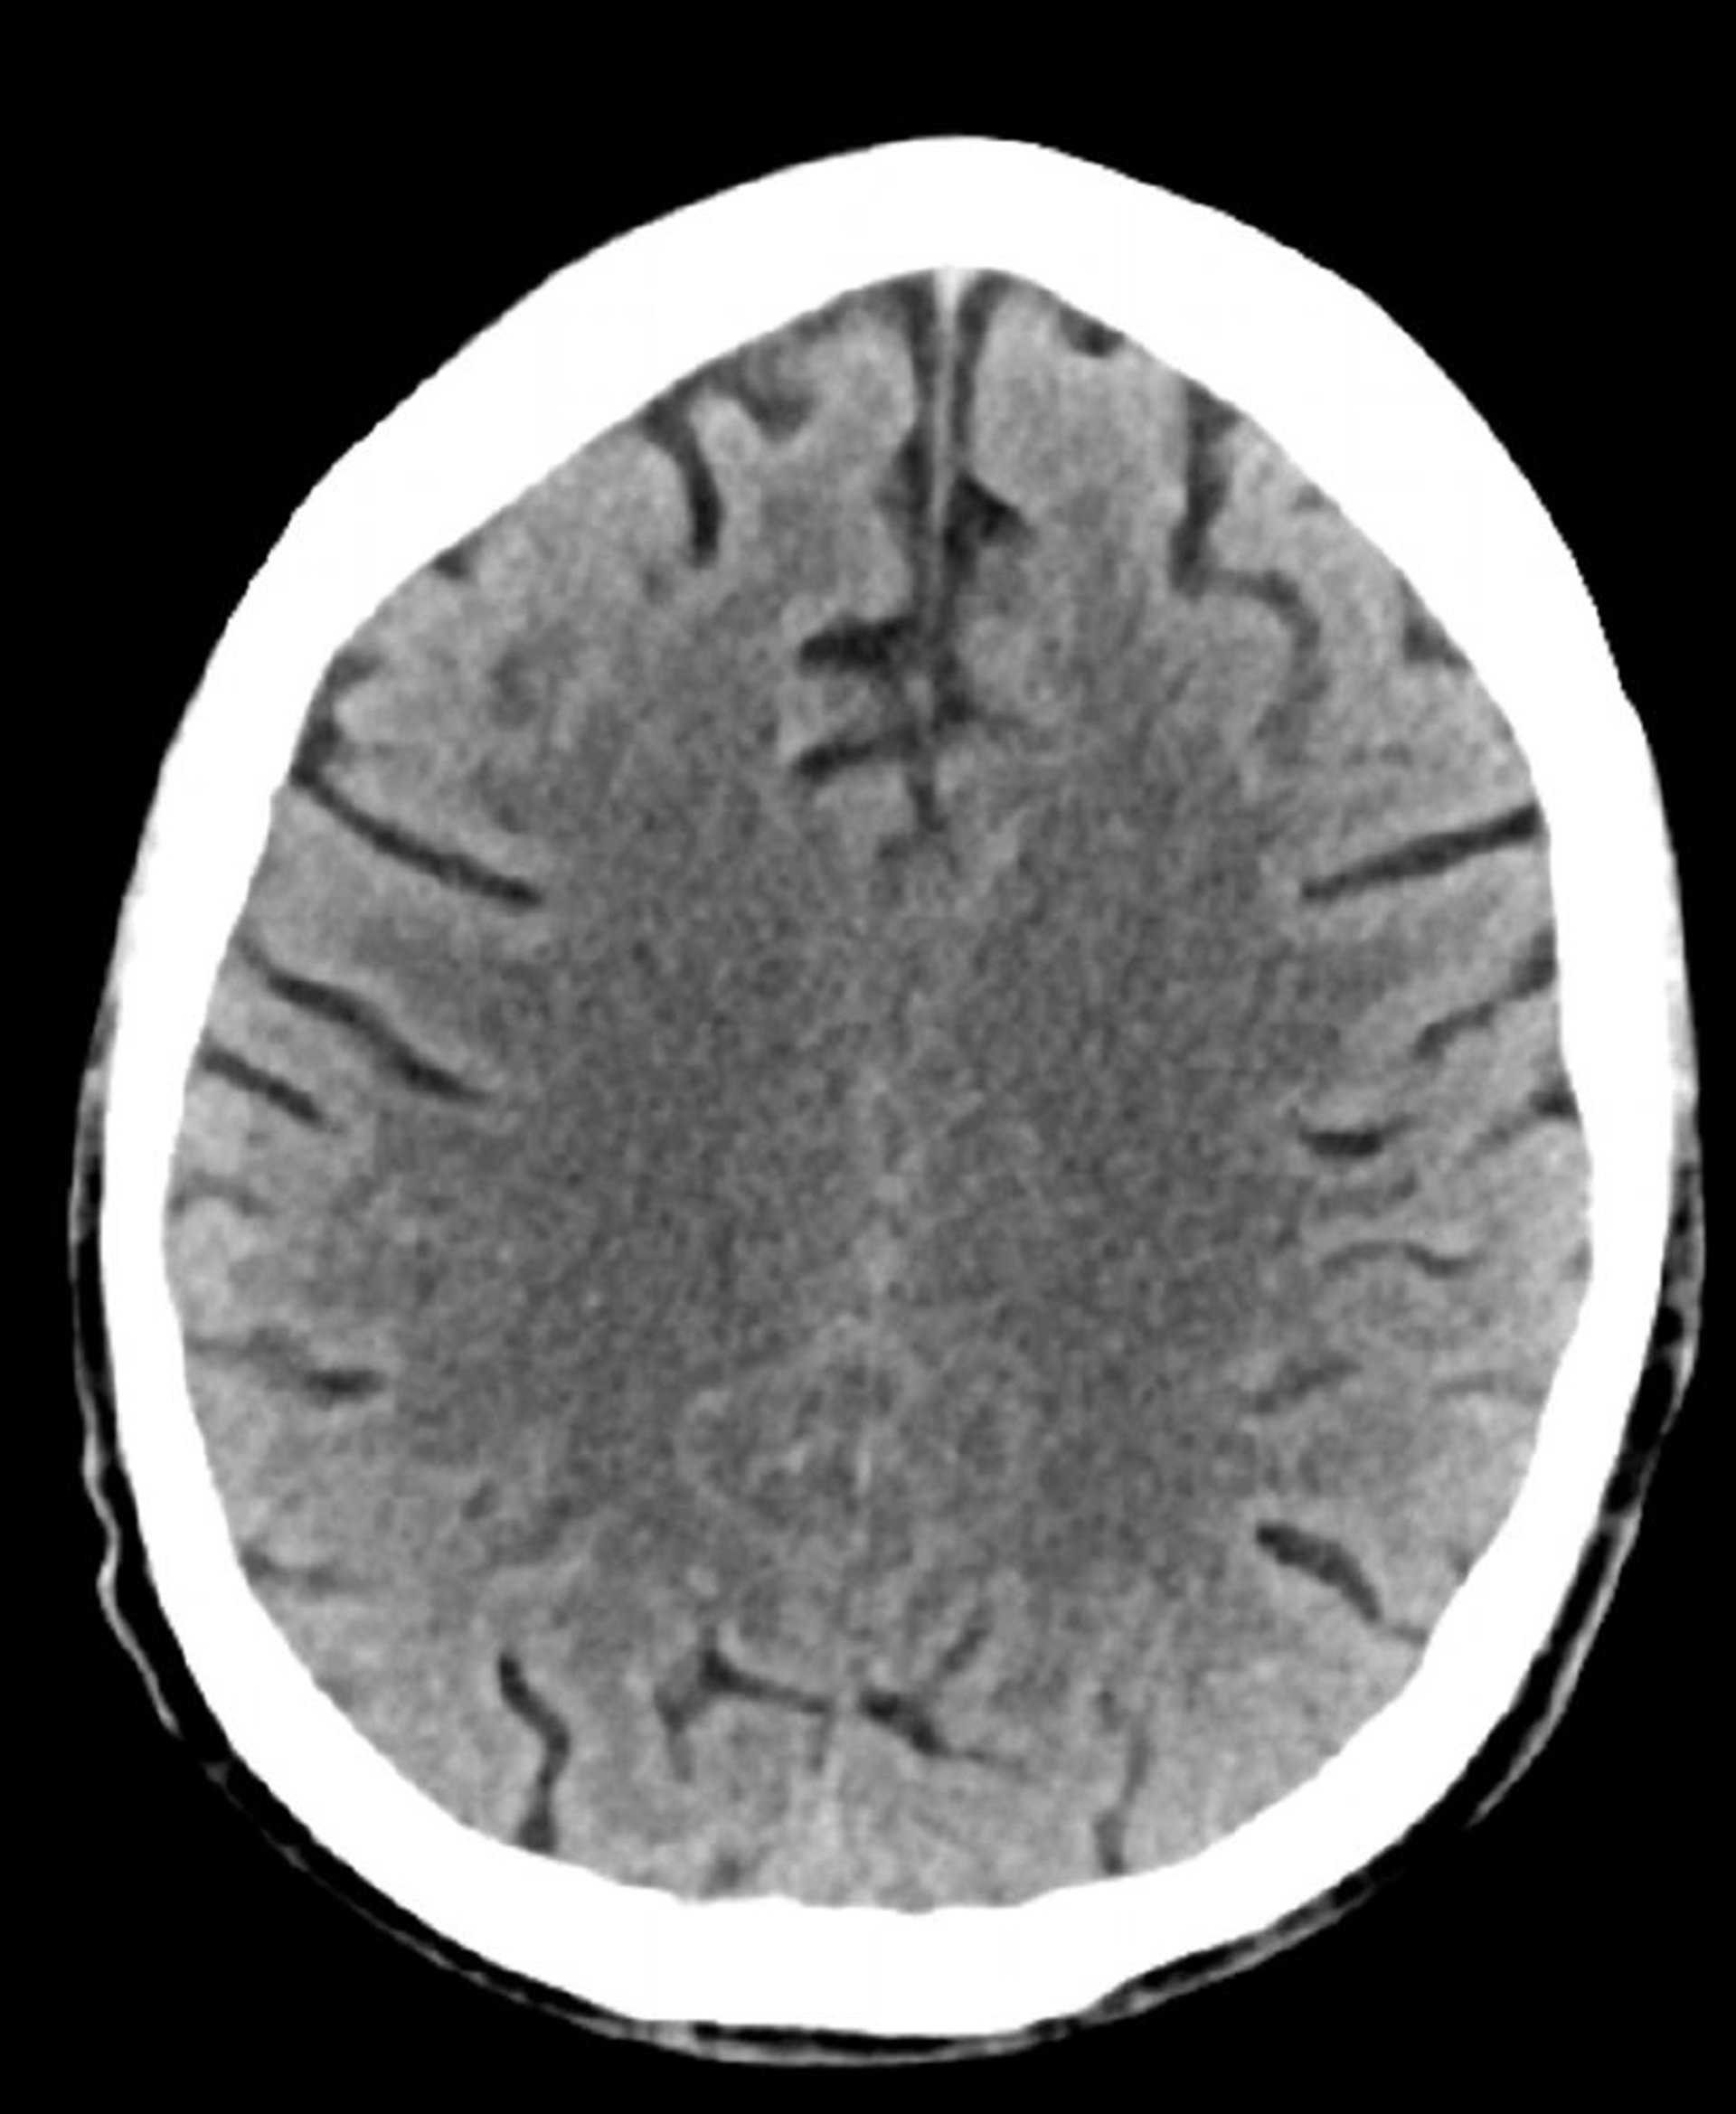

TC cerebrale normale (adulto di 74 anni), slide 2

Questa immagine è una normale TC della testa di un adulto di 74 anni. Rispetto alla normale TC della testa di un soggetto di 30 anni, i solchi sono più grandi. Questi reperti sono normali in questa fascia d'età.